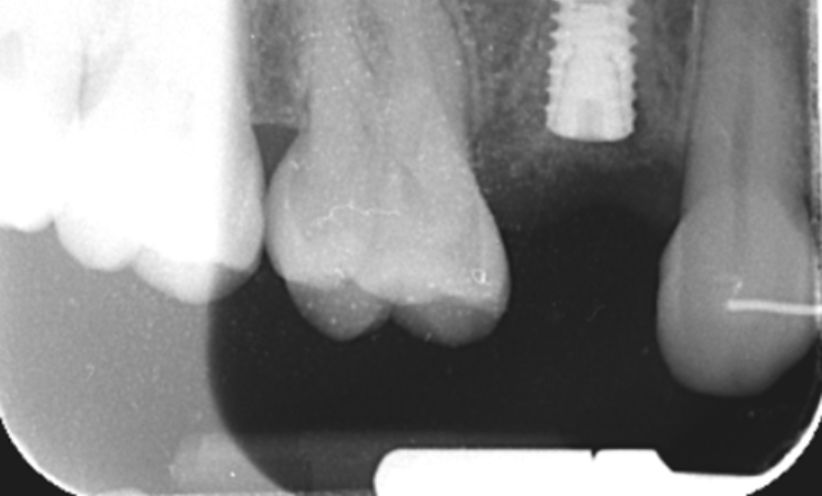

Case 31